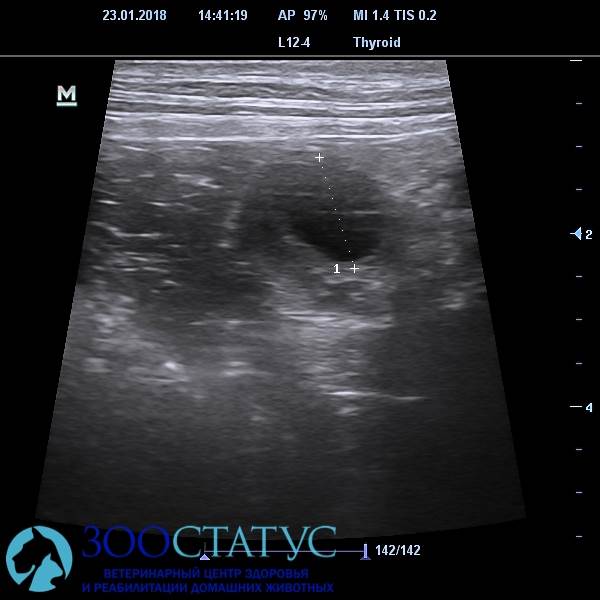

На УЗИ яичников мы можем видеть фолликулы, приблизительно подсчитать их, наблюдать их разрыв, то есть наблюдать овуляцию «онлайн». Но и у этого метода есть ограничения: яичники чрезмерно «округлой» или очень крупной собаку ( например упитанного алабая) рассмотреть непросто, сложность для визуализации могут представлять также газы, часто находящиеся в кишечнике собаки и особенности анатомического строения ( у плоских и длинных собак яичники прикрыты последними ребрами).